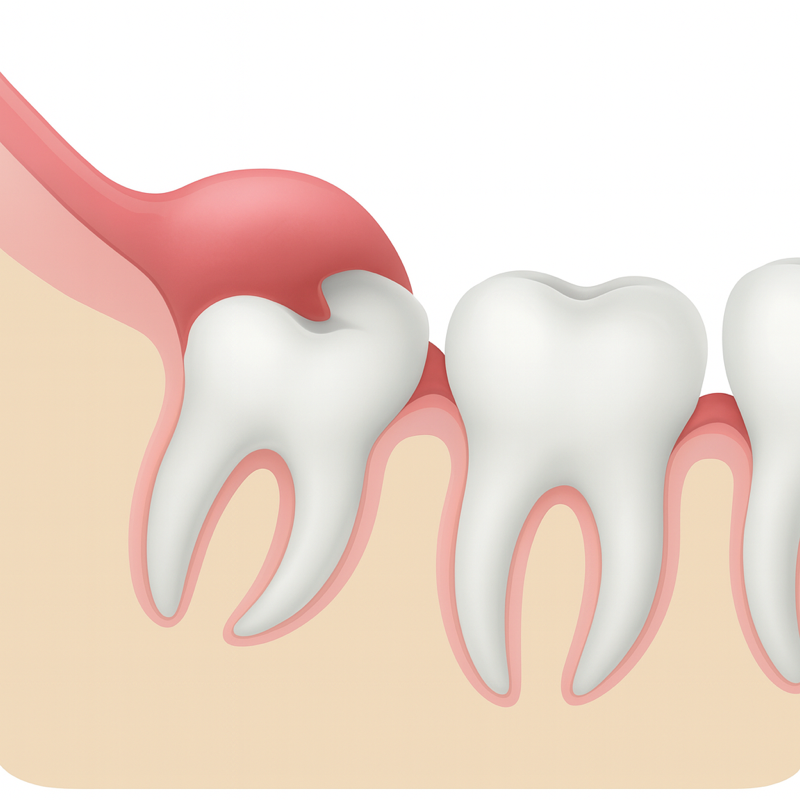

사랑니의 위치와 방향에 따른 분류입니다 (출처: https://www.pacificoralsurgeon.com/)

✔ ① 누워 나거나 반쯤만 나온 사랑니 (매복, Half-impacted)

이런 경우 음식물이 끼고

양치질이 거의 불가능해요.

염증, 통증, 심지어 옆 치아 뿌리 흡수까지

유발할 수 있기 때문에

이 형태는 대부분 발치가 필요해요.